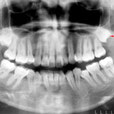

Cuatro pacientes jóvenes, acuden a la consulta para realizarse estudios radiográficos previo tratamiento ortodóntico. En la radiografía panorámica (fig. 1) se observa los terceros molares inferiores semiimpactados en posición horizontal. En la radiografía panorámica (fig. 2) se observa los cuatro terceros molares totalmente impactados; el tercer molar superior derecho se encuentra en posición vertical, el tercer molar superior izquierdo en posición mesioangular y los terceros molares inferiores en posición transversal. En la radiografía panorámica (fig. 3) los terceros molares superiores se encuentran totalmente impactados en posición vertical; el tercer molar inferior derecho semiimpactado en posición horizontal, el tercer molar inferior derecho en posición mesioangular y el tercer molar inferior izquierdo semiimpactado en posición mesioangular. En la radiografía panorámica (fig. 4) se observa el tercer molar inferior derecho totalmente impactado en posición invertida, el tercer molar inferior izquierdo semiimpactado en posición vertical.

Dientes impactados son aquellos que siguen formándose dentro del hueso pero fracasan en el proceso de erupción a causa de falta de espacio o por estar obtaculizados por alguna barrera física (quistes o tumores odontógenos). Cualquier diente puede estar impactado pero los más frecuentes son los terceros molares y los caninos superiores. Los terceros molares impactados se clasifican según su orientación dentro de la arcada dentaria , así se pueden presentar en posición mesioangular,distoangular,vertical, horizontal e invertida. Si se encuentran rodeados totalmente por hueso se consideran como impactados total y si se encuentran parcialmente en el hueso y parcialmente en tej. blando se consideran semiimpactados La impactación de los dientes muchas veces puede pasar inadvertida y se descubre mediante una radiografía , pero también pueden ocasionar complicaciones como reabsorción radicular del diente adyacente, infección, dolor asociado ,predisposición a la formación de quistes dentígeros y reabsorción externa